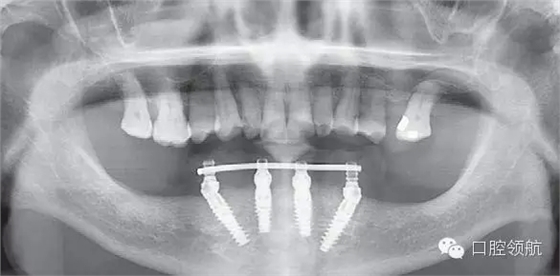

圖6-16為過渡義齒佩戴后的全景片。這張全景片的作用是確認螺絲固位過渡義齒的臨時內(nèi)冠復(fù)合基臺與復(fù)合基臺完全就位。如果全景片無法準確確認時,建議拍攝小牙片確認所有的臨時內(nèi)冠復(fù)合基臺就位完好。過渡義齒就位不良,是引起All-on-4種植體早期脫落的一個主要原因。確認就位后開始咬合調(diào)整。

圖6-16 下頜All-on-4過渡義齒戴牙后的全景片